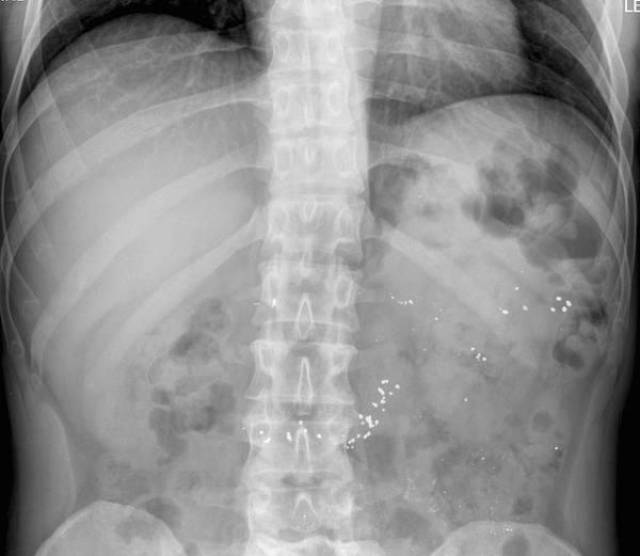

Nails. A lot of nails.